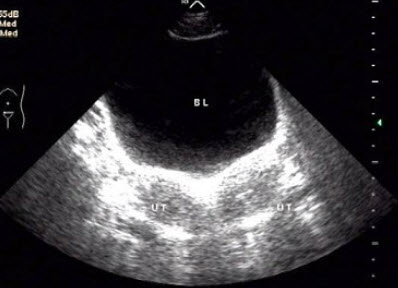

26、单项选择题

女,27岁,下腹部疼痛数月,体检:右侧附件区增厚、增大,B超检查如图所示,最可能的诊断为()

A.右侧卵巢囊肿

B.右侧输尿管扩张

C.右侧输卵管积液

D.盆腔积液

E.以上都不是